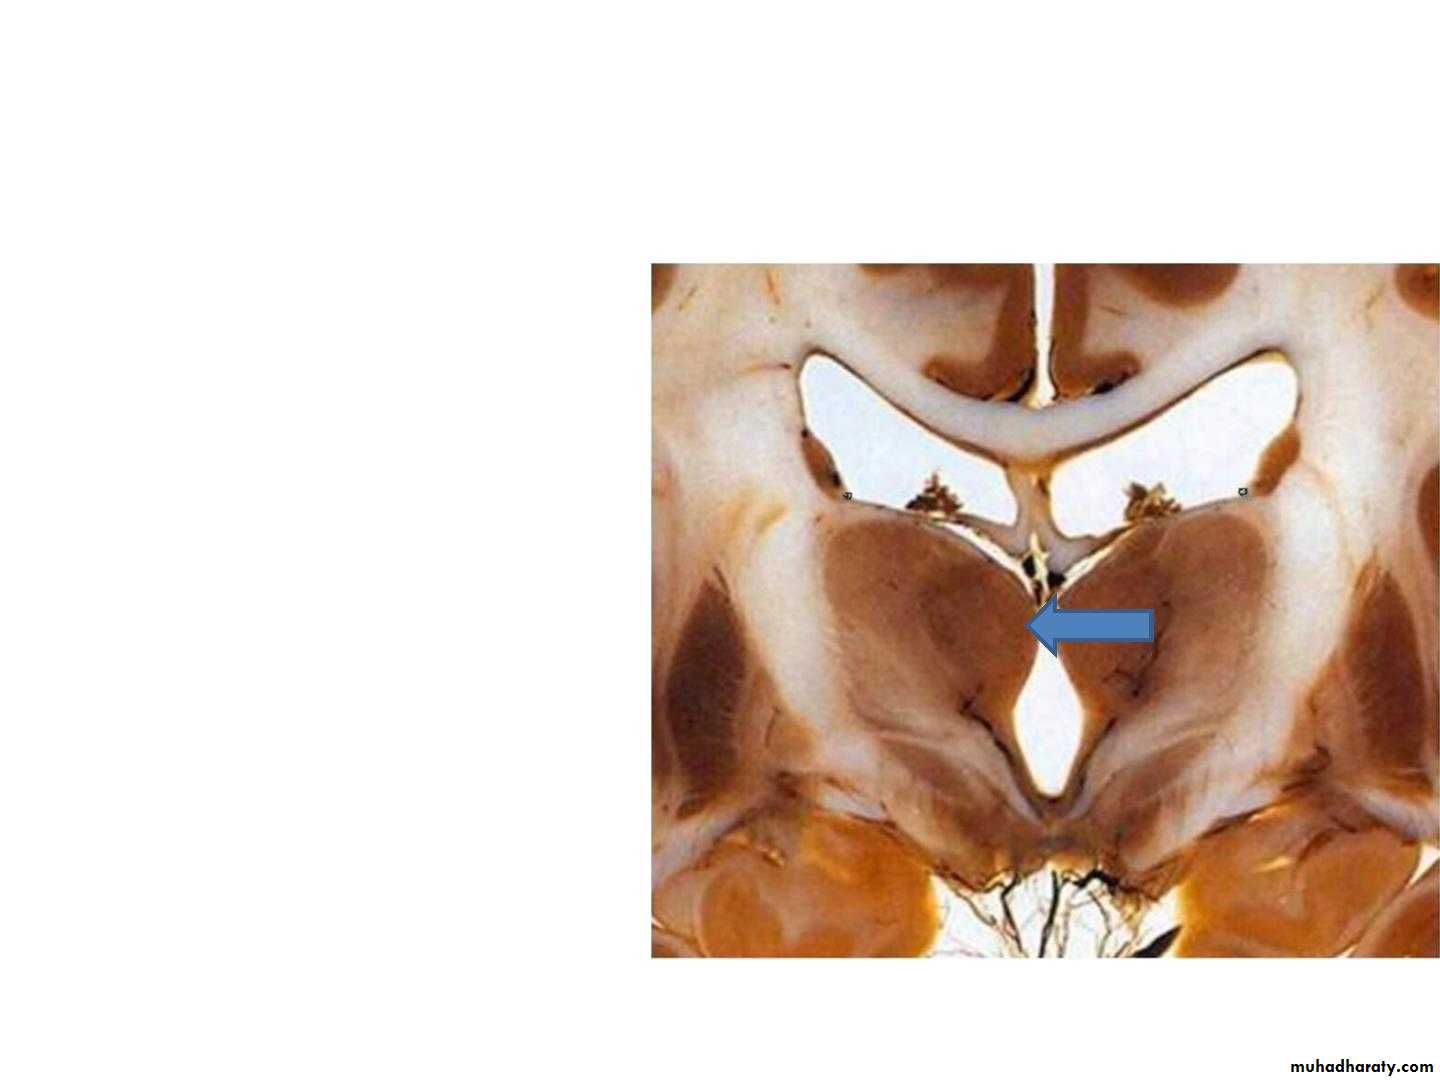

• Medial Surface

• • forms the upper 2/3 of the• lateral wall of the third

• ventricle.

• • It connects the medial

• surface of the other

• thalamus on the opposite

• side by a band of gray

• matter, the interthalamic

• connection (interthalamic

• adhesion).

• • It is covered by ependyma